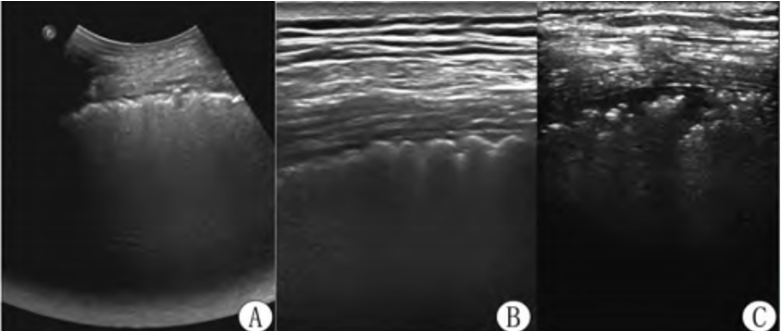

在了解异常肺超征象之前,应该先要知道正常肺部超声征象。进行肺部超声检查时,首先要确定胸膜的位置。将探头置于两个肋骨之间时,会看到屏幕外围两侧有宽约2 cm,厚约0.5 mm的高回声曲线,即胸膜线。正常的胸膜线是清晰、锐利、光滑、连续的。胸膜线位于屏幕中央,两侧肋骨下方,其形态类似蝙蝠,故称为“蝙蝠征”。还有肺滑动征(胸膜滑动征)、A线、M超模式下的沙滩征,这些都是正常肺部超声征象(图3)

图片

图3  正常肺部超声征象